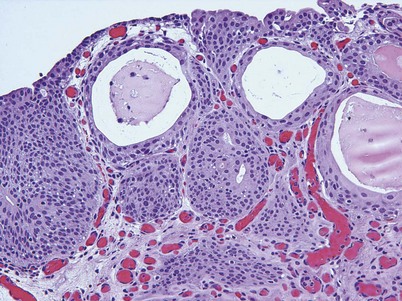

PUNLMP is a papillary growth with minimal cytological atypia that is more than seven cells thick and is generally solitary and located on the trigone (Fig. 80–9) (Holmang et al, 2001; Sauter et al, 2004). PUNLMP is composed of thin papillary stalks, where the polarity of the cells is maintained and the nuclei are minimally enlarged. PUNLMP has a low proliferation rate and is not associated with invasion or metastases, but almost 80% will have loss of chromosome 9 (Cheng et al, 2004). PUNLMP is different from a benign papilloma in that a PUNLMP has a thicker cell layer and large nuclei with occasionally mitotic figures. The male to female ratio for PUNLMP is 5 : 1, and the mean age is 65 (Holmang et al, 2001). PUNLMP can recur within the bladder in 35% of cases, but progression is rare, occurring in less than 4% (Oosterhuis et al, 2002).